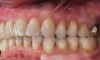

(27.) Postoperative view of implants after 3-weeks of healing.

Figure 27